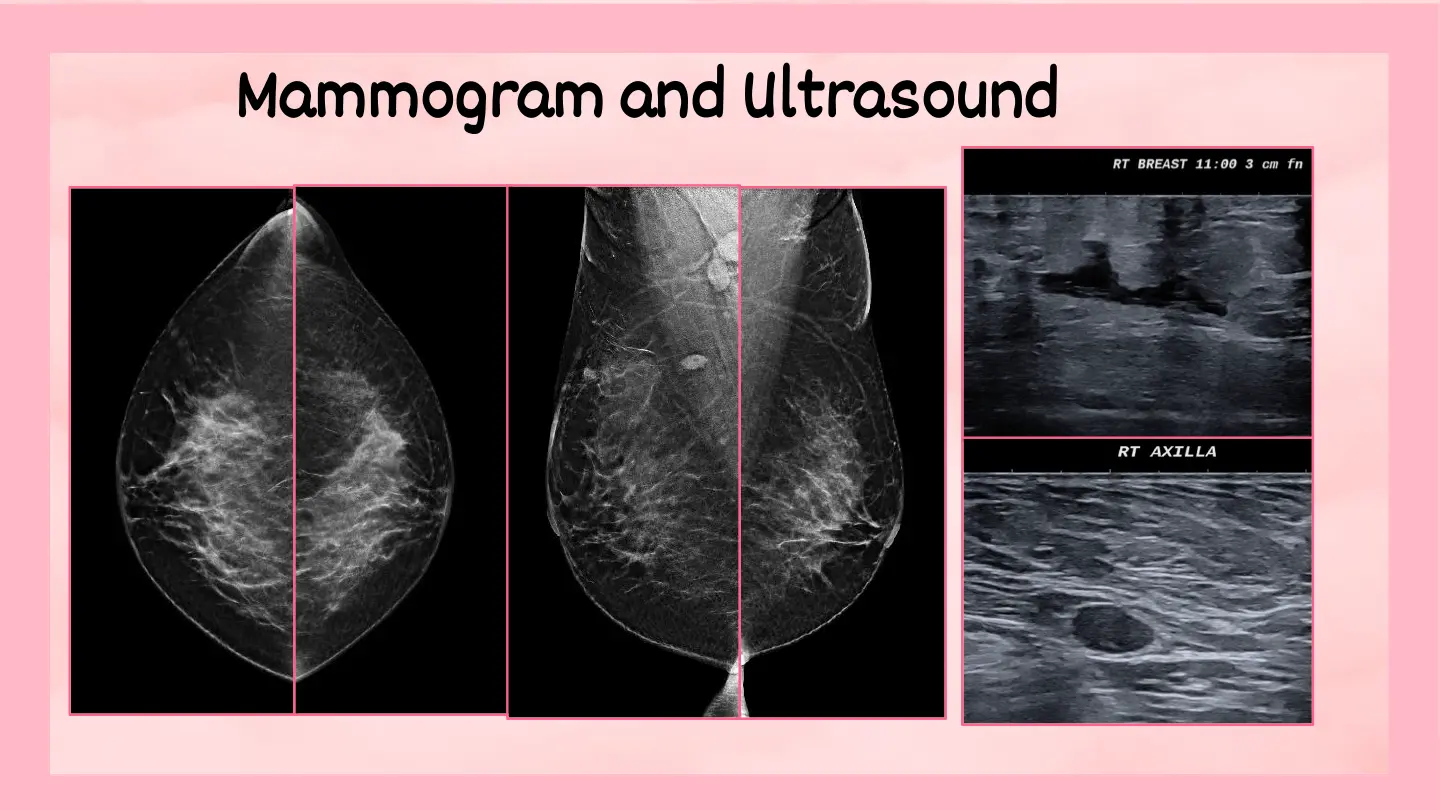

February 2026